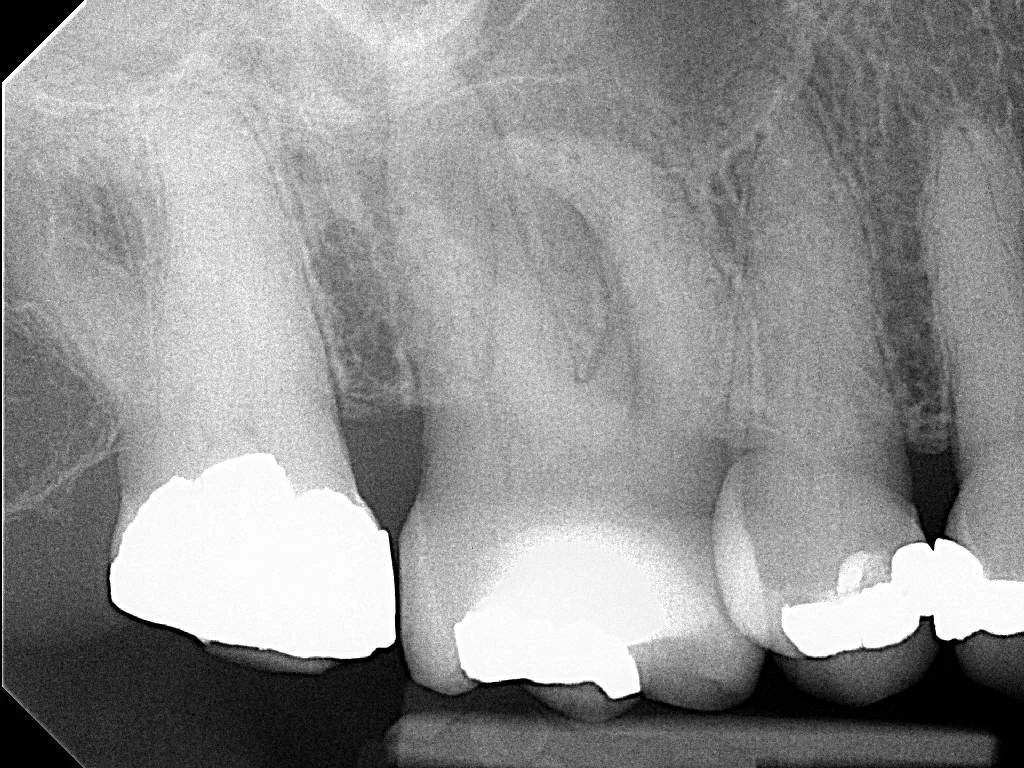

Pre-op PA revealing sclerosed canals on the UR6 and an apical radiolucency on the curved MB root